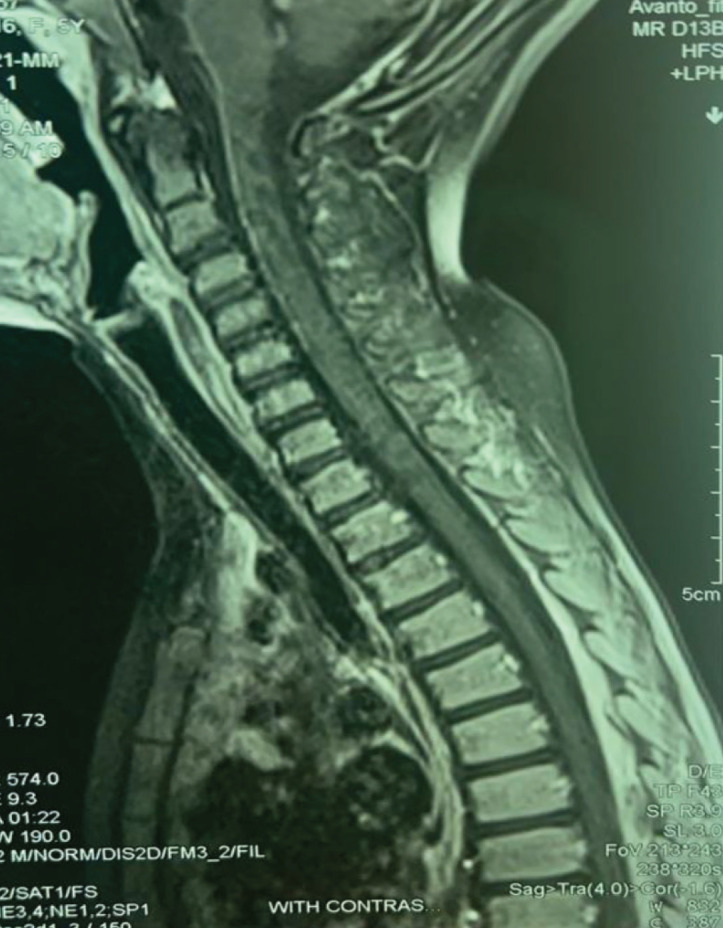

Brown-Vialetto-Van Laere syndrome (BVVLS) is a rare neurodegenerative disorder of childhood. According to the previous reports, it has various primary signs and symptoms. Because of the simple treatment with riboflavin supplementation, it is important to have suspicious to this disease and begin treatment even before genetic test confirm. We report a five-year-old girl with BVVLS that manifest with hearing problems, first. There was obvious improvement in her disease clinical signs with riboflavin supplementation treatment.

Abstract Image